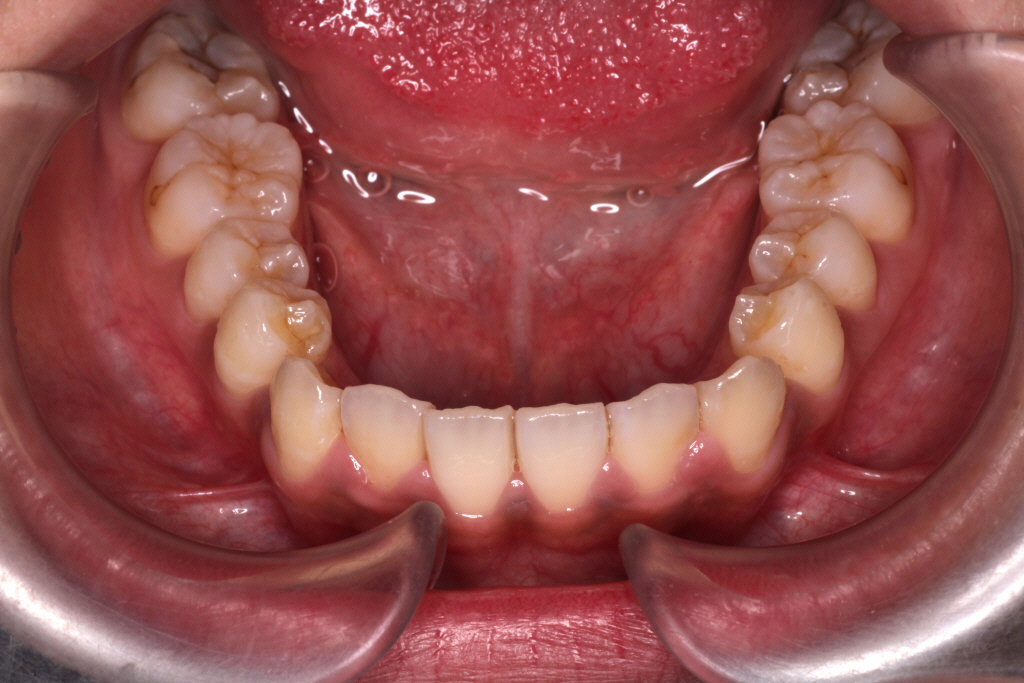

上下マウスピースを37枚最後まで1週間ずつ使い、6ヶ月後のお口の中の状態です。↓

① 左上の2番目の歯が歯列に入っていない

② 右上の2番目の歯が切端咬合と言って上下の歯の先端がぶつかっています。

③ 側方の上下の咬合関係が理想の上1本に対して下2本にはなっていません。

④ 左右の2番目、3番目あたりの噛み合わせがあまく、隙間がある。

このような症状を改善させるために、リファイメント2回目を行いました。